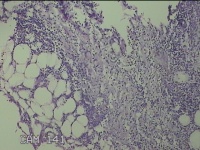

右侧腋下结节

性别

男

年龄

56岁

临床诊断

一般病史

标本名称

大体所见

灰白粉红色组织2.3x2x0.8cm一块,表面带梭形皮肤2.3x2cm,皮下见结节2x1cm一个,结节部分已切开,见结节呈囊性,囊内有少许灰白色角化物,囊壁厚0.1cm。

炎性病变。